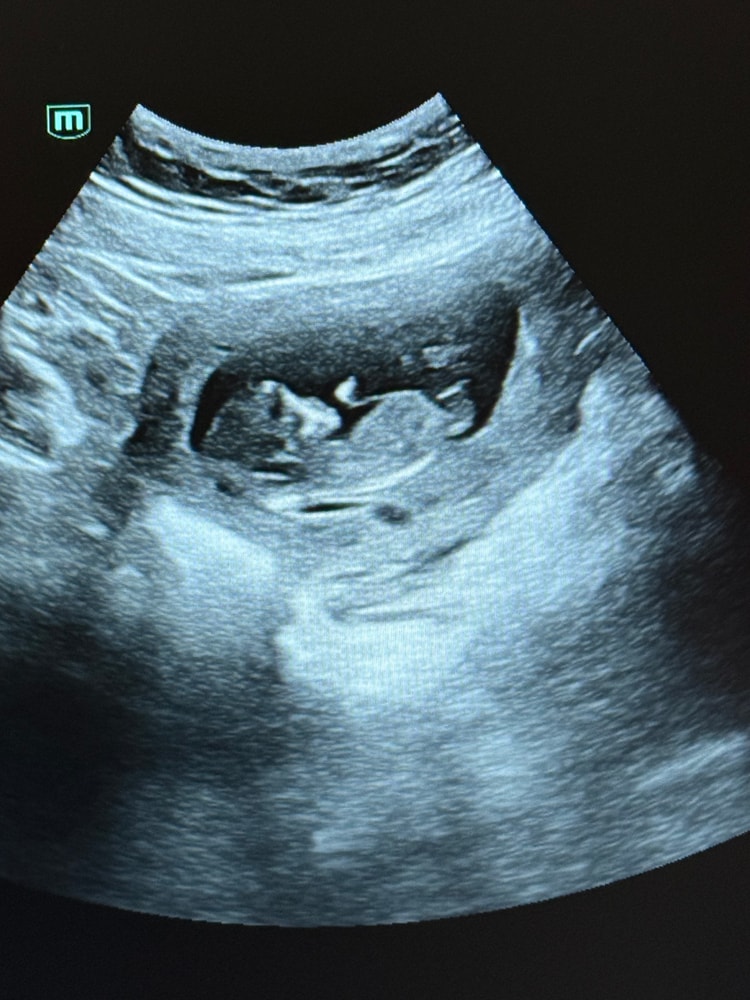

Евгения в Клуб беременных 2 месяца Первый скрининг Скрининг ну и естественно как не погадать на кого похоже? Ваши ставки?😂 Посмотрите еще 20 записей на эту тему Лучший ответ Екатерина Больше похоже на девочку 04.10.2025 Ответить Отменить Ответить Ornella Mutit Думаю девочка💗 04.10.2025 Ответить Марья Больше на девочку похоже) 04.10.2025 Ответить Вольфрамовая Мама Девочка 04.10.2025 Ответить Яна Если то что я вижу и есть половой бугорок,то девочка) 04.10.2025 Ответить Евгения Яна, вот и я думаю, он ли это😂 04.10.2025 Ответить Анна Мальчик ) 04.10.2025 Ответить Malvina Девочка)) 04.10.2025 Ответить Задние рога боковых желудочков Задержка развития плода Чаты Беременных Выберите чат: Январята-2026 Февралята-2026 Мартята-2026 Апрелята-2026 Майчата-2026 Июнята-2026 Июлята-2026 Августята-2026